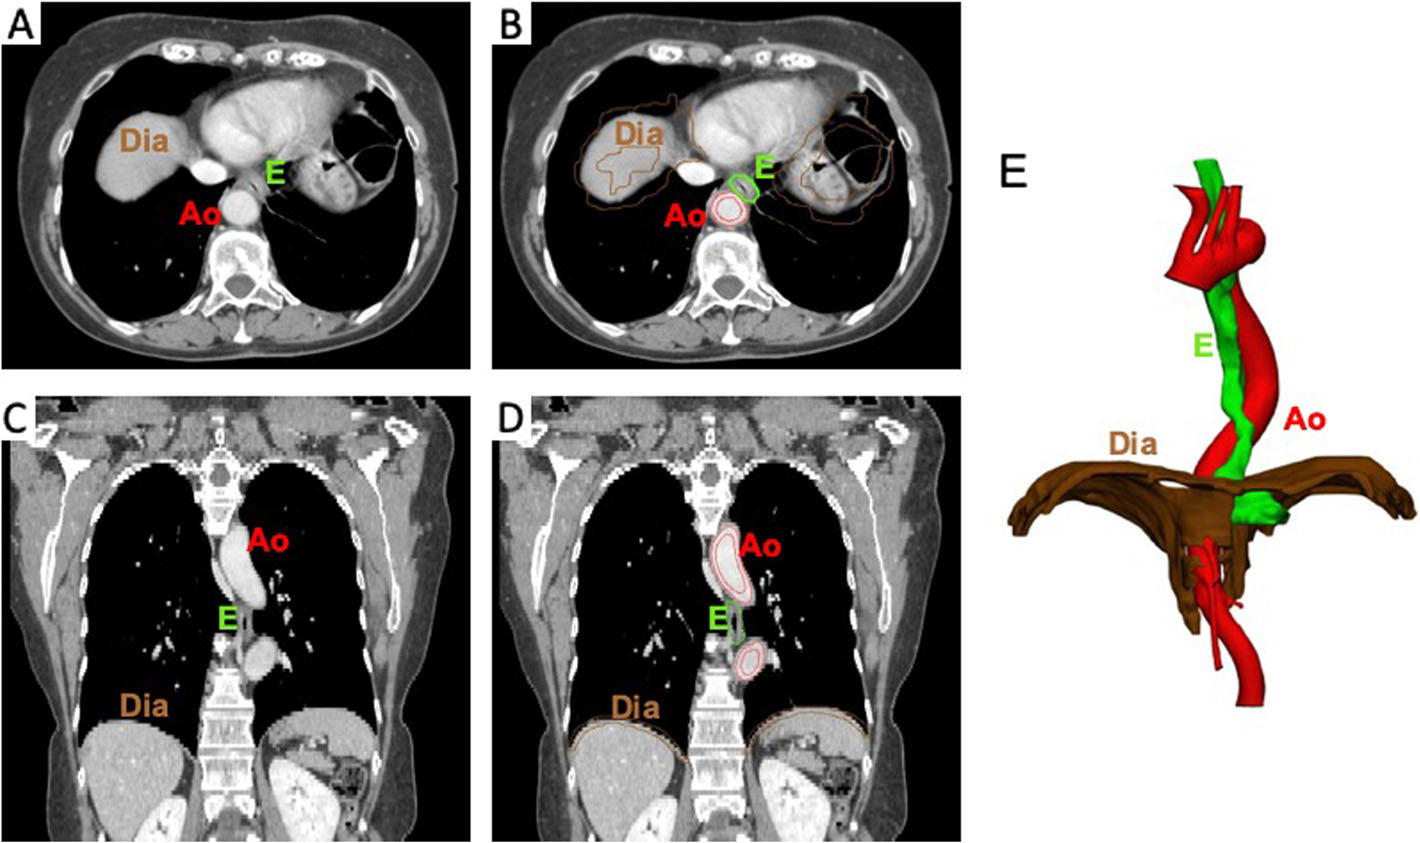

Rapport sur le premier cas d’utilisation de répliques anatomiques sur mesure pour soutenir la stratégie d’intervention avec le robot DaVinci®.

Quelques images